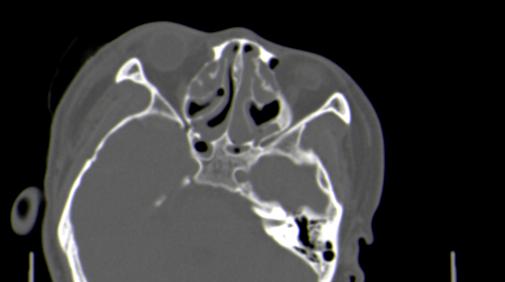

以下是引用皎皎白驹在2006-11-29 8:48:00的发言:[br]影像表现:双侧筛窦和上颌窦、鼻腔内均密度增高,右侧视神经增粗、弯曲,左筛窦顶部筛板及右侧纸板近视神经孔区可见骨折线。[br]结合临床表现考虑:右侧筛窦纸板近视神经孔区骨折致右侧视神经损伤。最好做个眼眶冠状扫描,更明确右侧视神经管是否狭窄。

以下是引用w_jianhua在2006-11-29 10:07:00的发言:[br]影像表现:双侧筛窦和上颌窦、鼻腔内均密度增高,右侧视神经增粗、弯曲,左筛窦顶部筛板及右侧纸板近视神经孔区可见骨折线。[br]结合临床表现考虑:右侧筛窦纸板近视神经孔区骨折致右侧视神经损伤。最好做个眼眶冠状扫描,更明确右侧视神经管是否狭窄。 [br] [br]支持[br]

以下是引用守望可可西里在2006-11-29 9:46:00的发言:[br][quote]以下是引用皎皎白驹在2006-11-29 8:48:00的发言:[br]影像表现:双侧筛窦和上颌窦、鼻腔内均密度增高,右侧视神经增粗、弯曲,左筛窦顶部筛板及右侧纸板近视神经孔区可见骨折线。[br]结合临床表现考虑:右侧筛窦纸板近视神经孔区骨折致右侧视神经损伤。最好做个眼眶冠状扫描,更明确右侧视神经管是否狭窄。